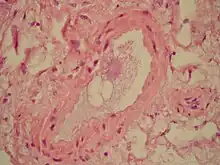

| Microscopic section of the lungs showing a blood vessel with fibrinoid material and an empty space indicative of the presence of lipid dissolved during the staining process. Haematoxylin and eosin stain | |